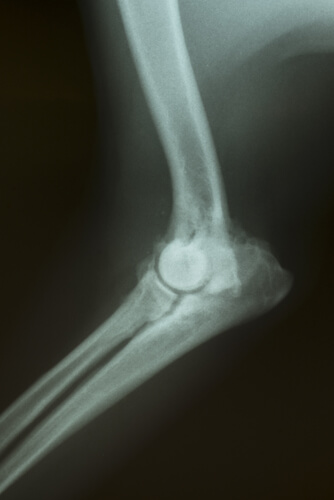

Dependiendo del tipo de síntomas, podrán ser necesarios algunos exámenes para determinar la causa del problema. Se podrán realizar análisis de sangre, radiografías, ultrasonidos, tomografías, etc.

- Finalmente, en el caso de los huesos y la médula ósea es posible realizar la biopsia con la ayuda de agujas especiales.